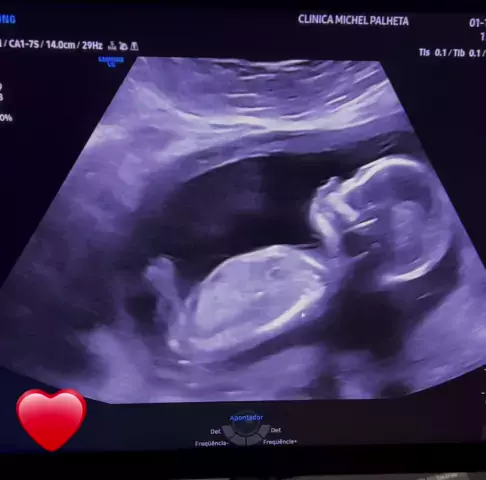

Dr. Michel Palheta

Ultrassonografia obstétrica